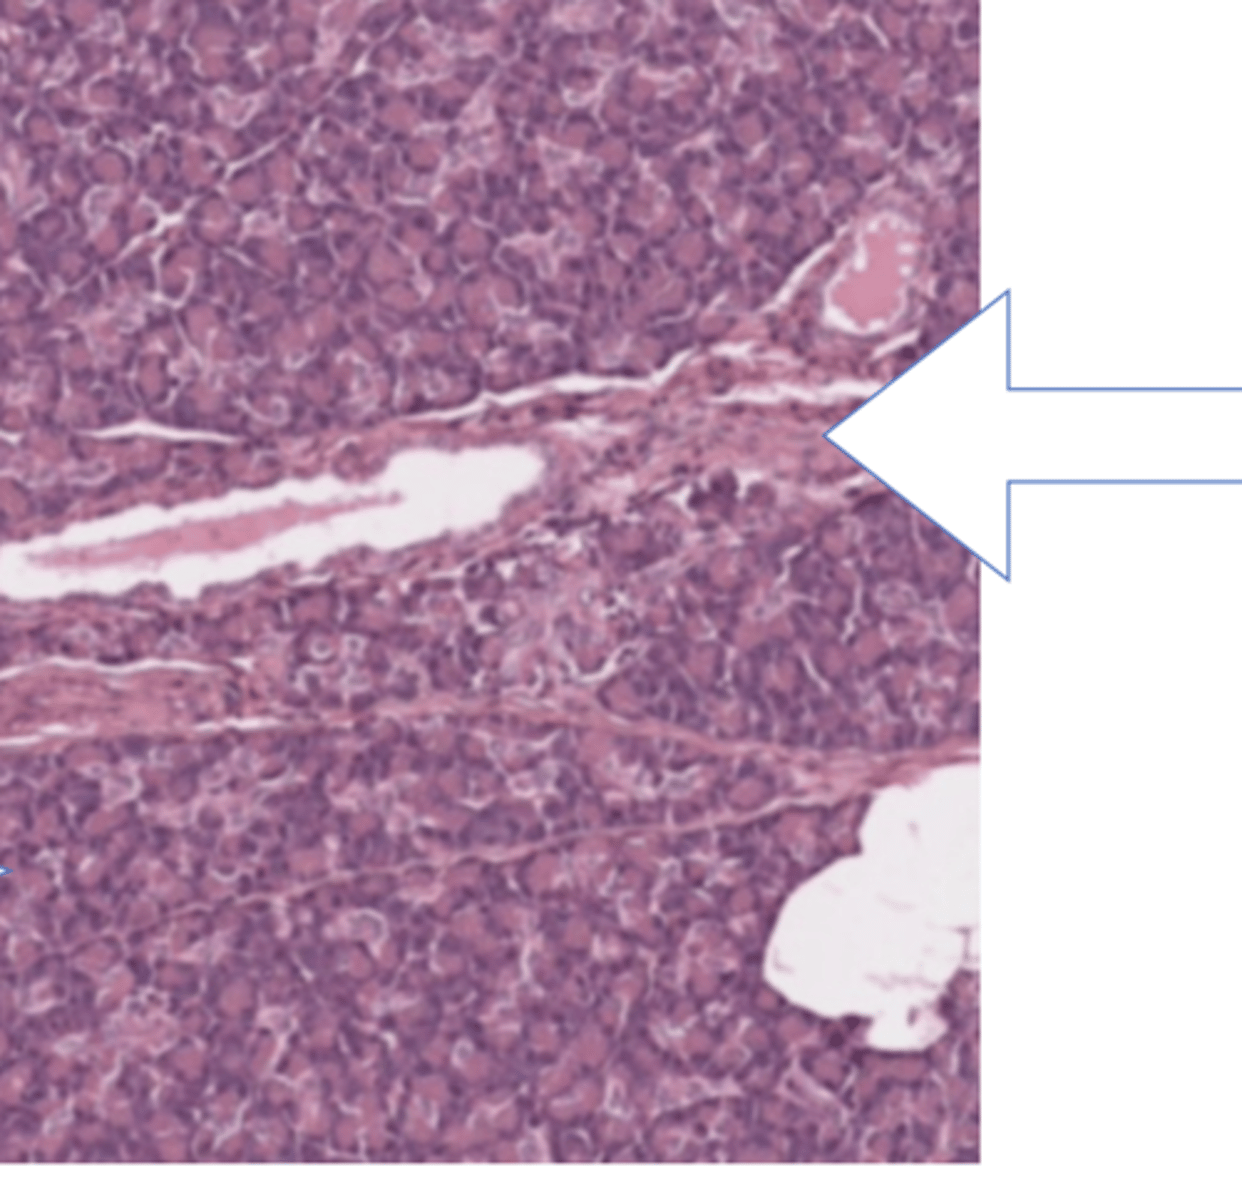

liver lobule

central vein of liver lobule